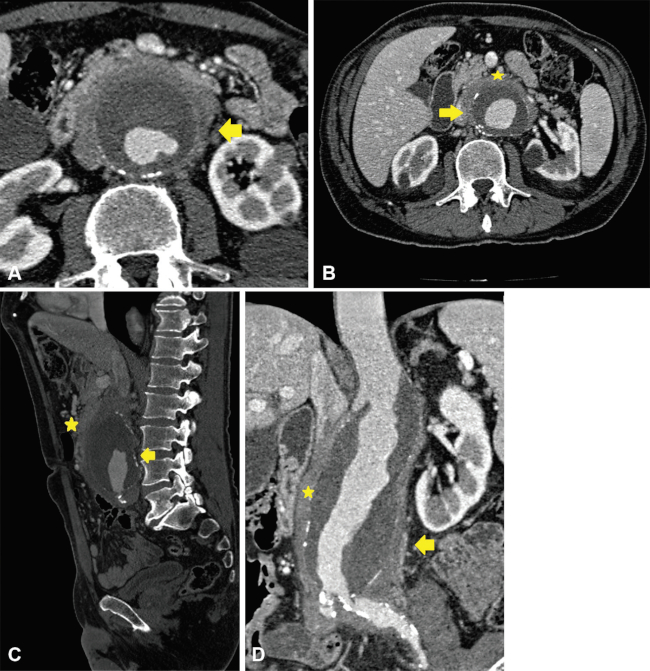

Pseudoaneurisma micótico

Con el término “micótico” se hace referencia a los aneurismas que son ocasionados por un proceso infeccioso. Es altamente infrecuente (prevalencia de 0,06% a 2,6%) y potencialmente fatal si no es tratado a tiempo.1

Son consecuencia de una infección que debilita la pared formando una falsa luz o pseudoaneurisma. La localización más común es la aorta infrarrenal, seguida de la aorta descendente y el patógeno mayormente implicado es Salmonella.

En la TCMD, se observan aneurismas con forma sacular en 90% de los casos y gas perianeurismático. Puede llegar a encontrarse destrucción vertebral, abscesos en el músculo psoas e infartos renales (►Fig. 6 and 7).1

Aortitis sifilítica

La sífilis es una enfermedad sistémica de transmisión sexual causada por Treponema Pallidum. El estadio terciario de la enfermedad se manifiesta entre 5 y 30 años después de la infección primaria y se caracteriza por compromiso neurológico y cardiovascular (aortitis, aneurisma, valvulitis aórtica con regurgitación y estenosis de arterias coronarias).2 La invasión de la adventicia de la aorta causa endarteritis obliterante de la vasa vasorum, con el consecuente hipoflujo vascular, debilidad de la pared y formación de un aneurisma. Afecta la aorta ascendente en 60% de los casos y el cayado aórtico en 30% de los casos.1